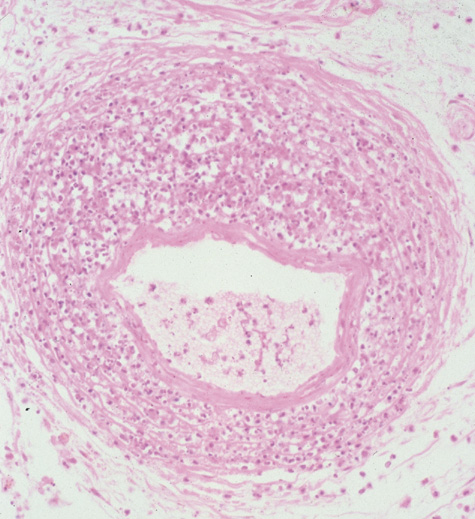

Rhinocerebral mucormycosis originates as a rhinitis, parapharyngitis, or sinusitis, and spreads by invasion of blood vessel walls, causing a necrotizing vasculitis with thrombosis of the vascular lumina and resultant infarction. The patient typically presents with unilateral orbital apex syndrome, including severe pain, visual loss, total ophthalmoplegia, corneal anesthesia, and multiple cranial nerve palsies.127 Orbital cellulitis presenting with early visual loss is one of the hallmarks of mucormycosis.72 Gangrene may occur of external periorbital tissues as well as of the hard palate and nose, and eschar-like crusting may be observed within the nose or on the hard palate (Fig. 23). Obstruction of the central retinal artery, ciliary arteries, and choroidal circulation can also be seen.124,125 Brain damage may occur because of spread of infection or infarction or occlusion of affected intracranial vessels.72

CT shows sinusitis with or without bone destruction and is indistinguishable from other causes of orbital cellulitis.128 MRI may show carotid narrowing, occlusion, and absent flow in the superior ophthalmic vein (Fig. 24).72

Fig. 24. Mucormycosis. A. A 72-year-old patient with acute myelogenous leukemia and invasive fungal sinusitis presented with orbital cellulitis. B. Involvement of hard palate with eschar. C. Fungi in the posterior ciliary artery.

Diagnosis is made by having a large index of suspicion and obtaining specimens of nasal turbinate, sinus, or infected orbital tissue. Large, branching nonseptate hyphae are readily apparent on hematoxylin and eosin staining or with methenamine silver staining (see Fig. 23). These hyphae can be grown on fungal culture.